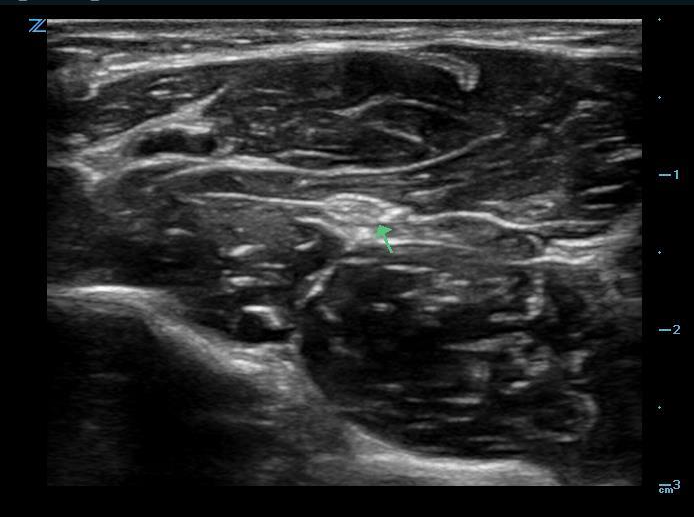

Figure 1. Median nerve in the mid-forearm